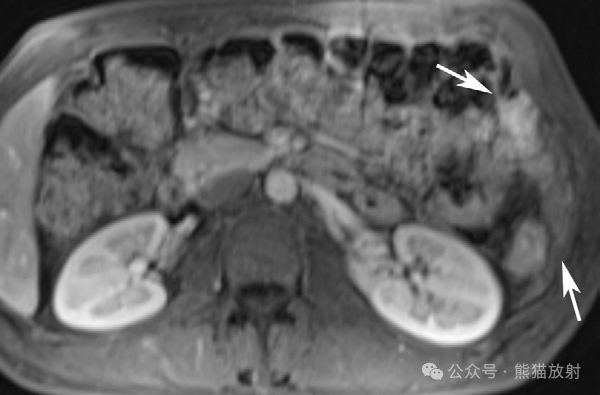

不同类型腹膜间皮瘤两例。(A,B) 46岁男性,湿型上皮样腹膜间皮瘤。腹盆部轴位(A)和冠状 (B) 对比增强 CT 图像显示腹膜不规则增厚,网膜饼形成 (箭)和严重腹水(箭头)。(C,D) 56岁女性,干型上皮样腹膜间皮瘤。腹部轴位增强 CT (C) 和T2WI (D) 图像显示大网膜明显饼状增厚 (箭)。